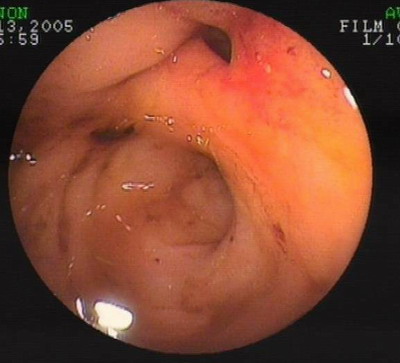

胶囊内镜结果显示:

空回肠交界处黏膜隆起,中心略凹陷,未见活动出血。

胶囊内镜

胶囊内镜图片